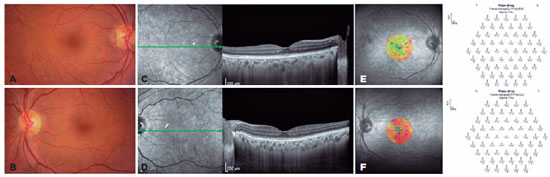

A 66-year-old woman had a history of breast cancer treated 13 years earlier with lumpectomy, radiotherapy, and chemotherapy followed by 5 years of tamoxifen therapy. She was in remission, but after an uneventful cataract surgery, she began to complain of photophobia and decreased vision. Her best-corrected visual acuity (BCVA) was 20/100 in the right eye (oculus dexter [OD]) and 20/800 in the left eye (oculus sinister [OS]). Her pre-cataract surgery BCVA was 20/40 in both eyes (oculus uterque [OU]). The ophthalmologic examination result was unremarkable (Figure 1A, B). The retinal nerve fiber layer was normal in OU on optical coherence tomography (OCT), and macular OCT revealed an asymmetrical granular aspect of the inner/outer photoreceptor layer (IS/OS layer) and ellipsoid zone in OU (Figure 1C, D). Microperimetry revealed good fixation stability and abnormal macular integrity in OU. The mean threshold was 21.8 dB for the OD and 12.6 dB for the OS (Figure 1E, F). Multifocal electroretinography (ERG) showed an abnormality in OU, showing an asymmetrical reduction in central response (Figure 1G, H).